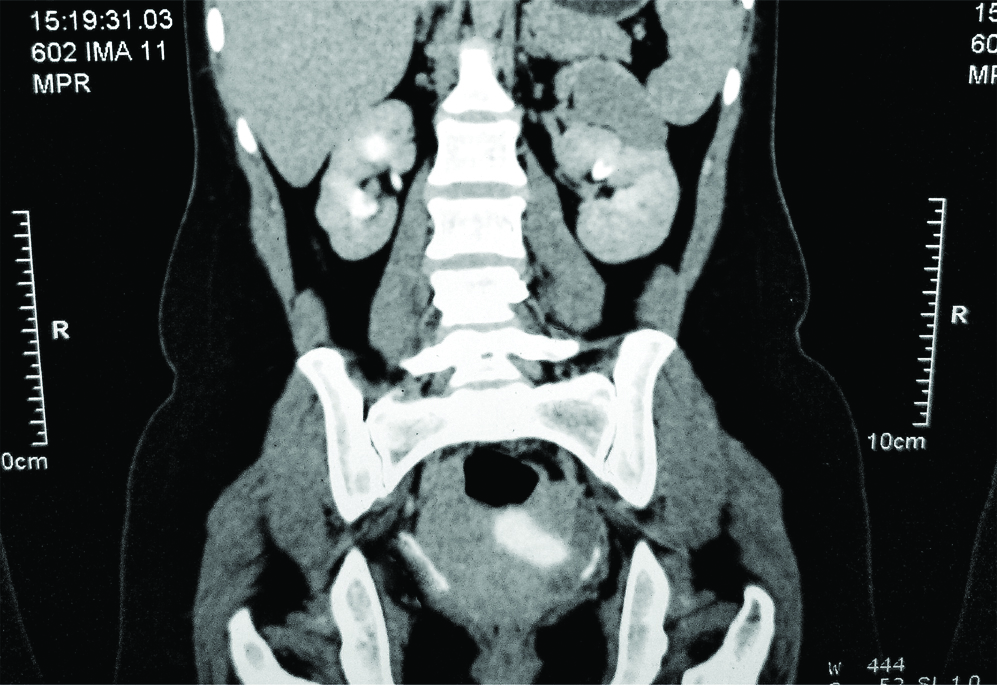

On follow-up, the patient was doing well. Patient was continent even at one year. The follow-up CT scan showed resolution of Hydronephrosis (HDN) on right side to mild degree with persistent hydronephrosis on left side, without any emergence of symptoms on that side [Table/Fig-4].

Postoperative CT images on follow-up-decreased hydronephrosis on right side.